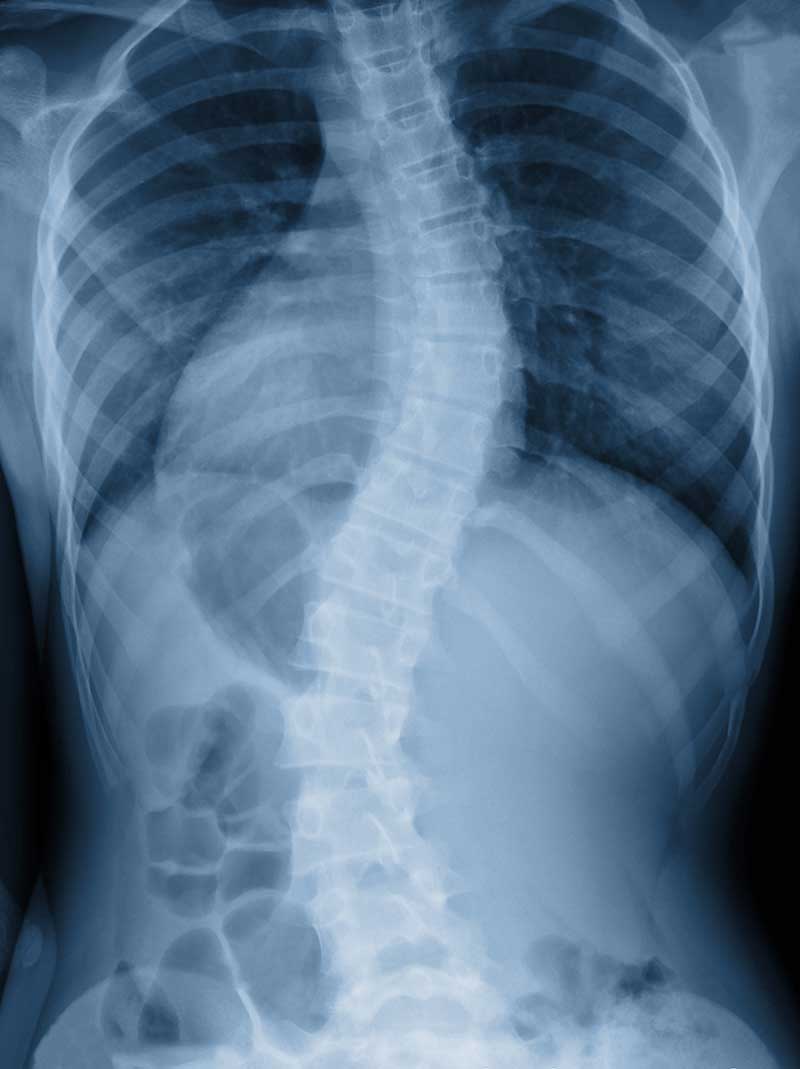

When detected early, scoliosis can be managed and treated to prevent the problem from getting worse. With scoliosis, the spine has abnormal curvatures to the side or even twists. Most cases of scoliosis appear for unknown reasons as scoliosis tends to develop before puberty in adolescence, in children who previously had no spine issues.

Many cases of scoliosis do not require surgery or extensive treatment, but if the curvature becomes more severe, medical intervention may be needed. Scoliosis appears equally in boys and girls, but typically girls are more likely to develop significant curvature that warrants treatment.